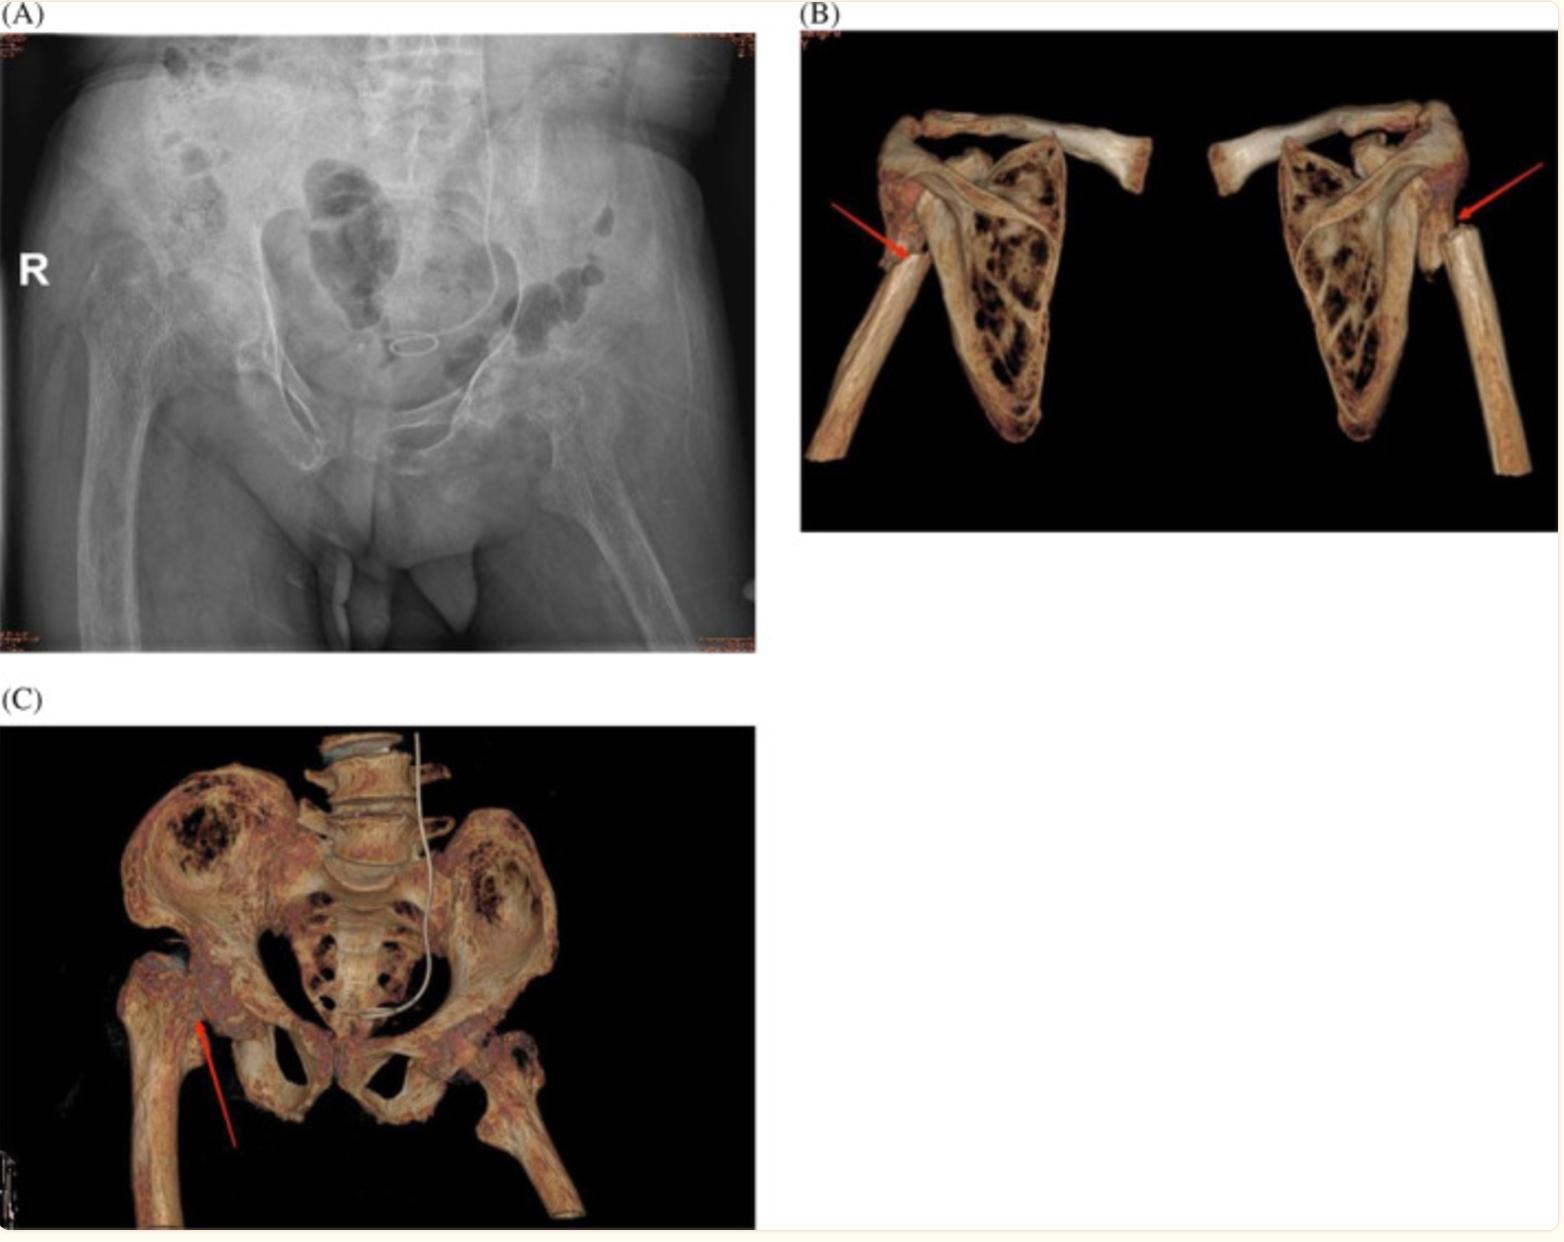

骨盆X光片显示右股骨颈骨折,左髋关节周围肌肉萎缩(图2A)。肩关节和骨盆的三维CT扫描显示双侧肱骨干骨折、右股骨颈骨折以及肩关节和盆腔组成骨的骨密度下降(图2B,C)。腹部CT扫描显示两个肾脏有多处腹腔内结石。

图2 (A) 骨盆X光片,显示右股骨颈骨折和左髋周围肌肉萎缩;(B) 肩关节三维计算机断层扫描(CT),显示双侧肱骨干骨折;(C) 骨盆三维CT,显示右股骨颈骨折,对齐良好